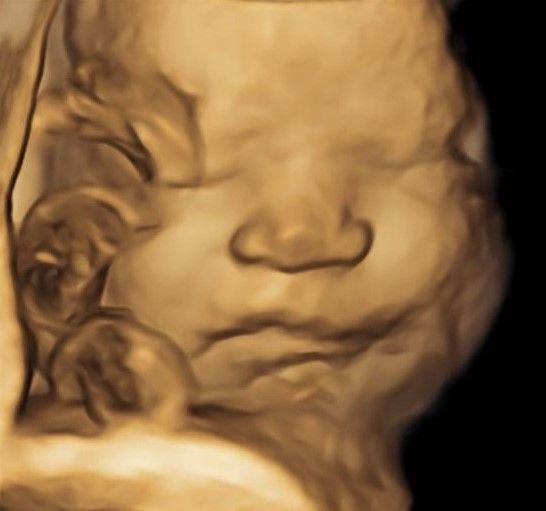

Eseguo in particolare ecografie ostetriche e ginecologiche anche in 3D e 4D per meglio identificare la problematica, offrire diagnosi precise ed un trattamento mirato e personalizzato.